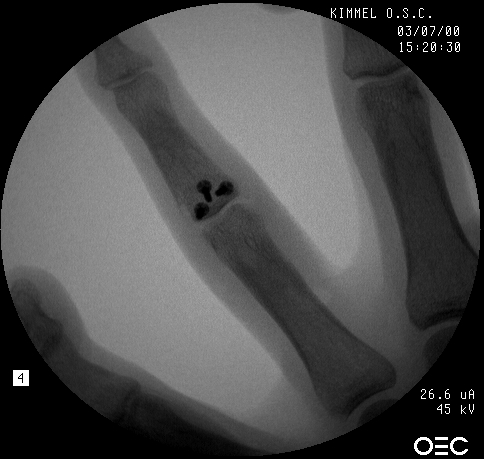

Xrays show a comminuted dorsal fracture dislocation of the proximal interphalangeal joint with dorsal subluxation.